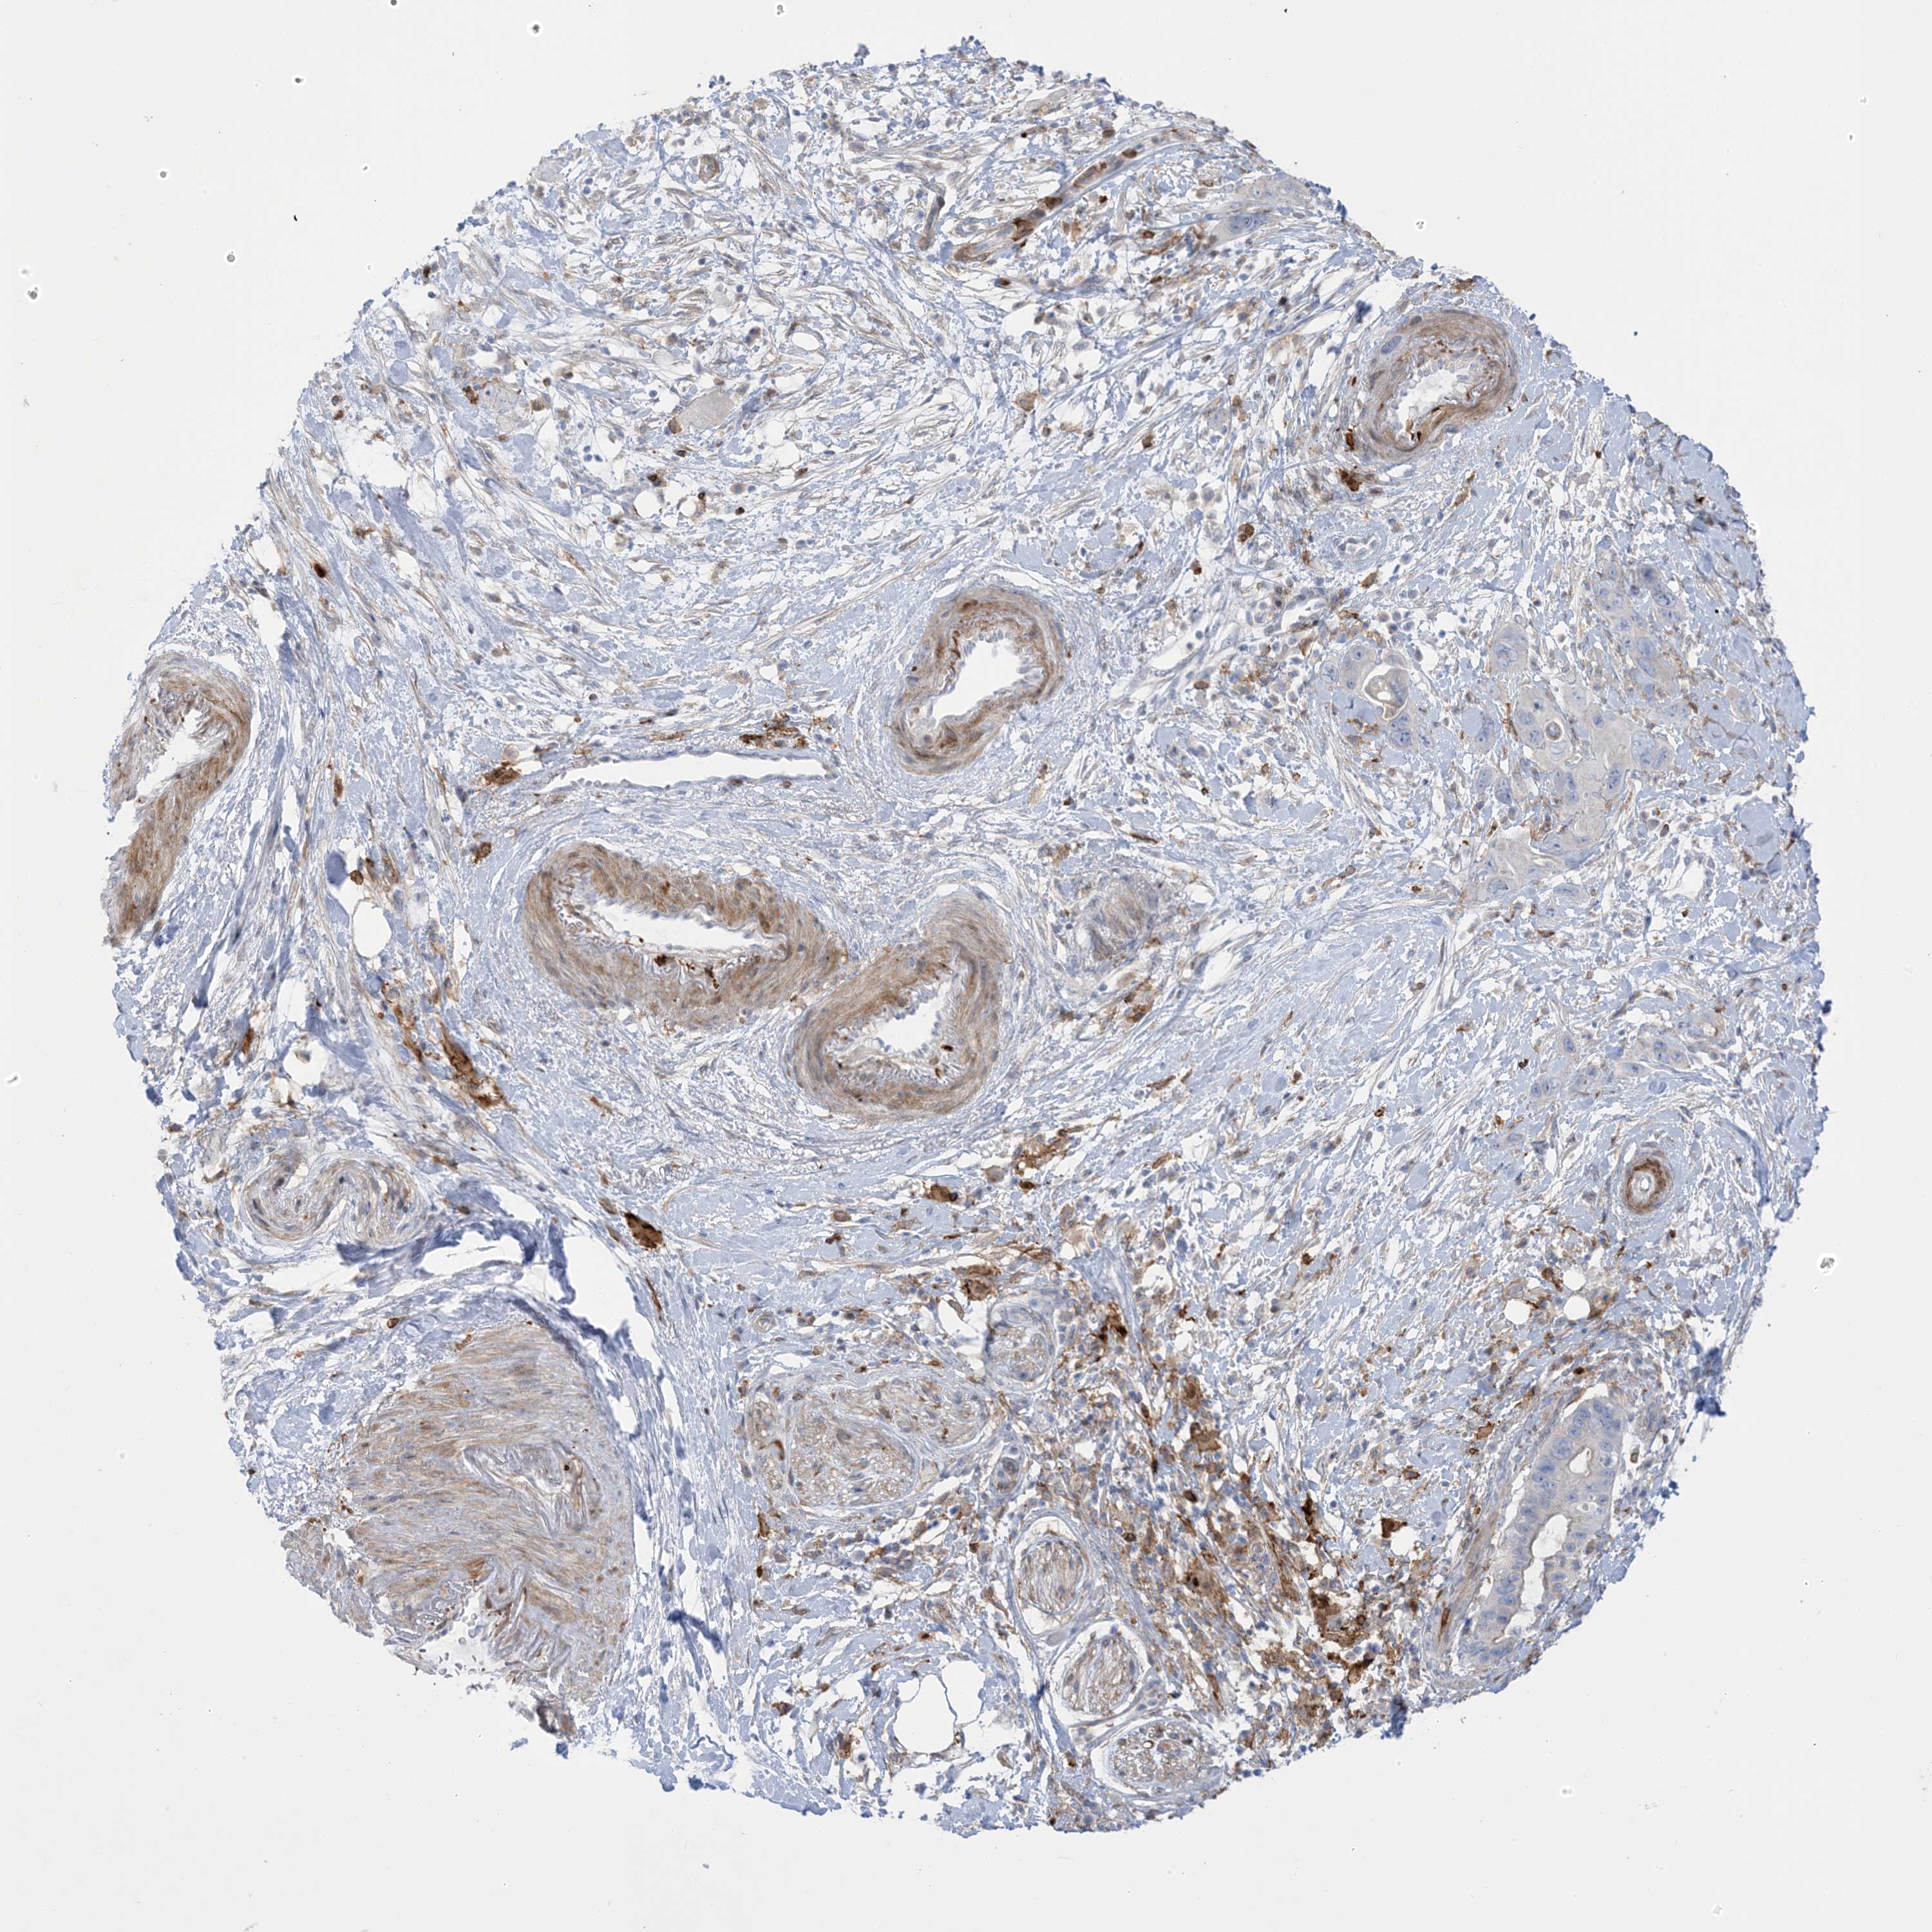

PANCREATIC CANCER - Protein expressioni

A mouse-over function shows sample information and annotation data. Click on an image to view it in a full screen mode. Samples can be filtered based on level of antibody staining by selecting one or several of the following categories: high, medium, low and not detected. The assay and annotation is described here.

Note that samples used for immunohistochemistry by the Human Protein Atlas do not correspond to samples in the TCGA dataset.

Antibody stainingi

Antibody staining in the annotated cell types in the current human tissue is reported as not detected, low, medium, or high, based on conventional immunohistochemistry profiling in selected tissues. This score is based on the combination of the staining intensity and fraction of stained cells.

Each image is clickable and will lead to virtual microscopy that enables deeper exploration of all samples and also displays staining intensity scores, fraction scores and subcellular localization as well as patient and tissue information for each sample.

Antibody HPA032024

Antibody HPA032025

Staining

High

Medium

Low

Not detected

Intensity

Strong

Moderate

Weak

Negative

Quantity

>75%

75%-25%

<25%

None

Location

Nuclear

Cytoplasmic/membranous

Cytoplasmic/membranous,nuclear

Adenocarcinoma, NOS